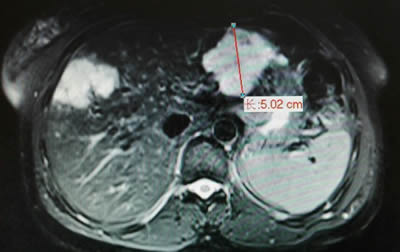

术前影像学发现右肝7×5cm的肝血管瘤 术前影像学发现左肝5×4cm的肝血管瘤